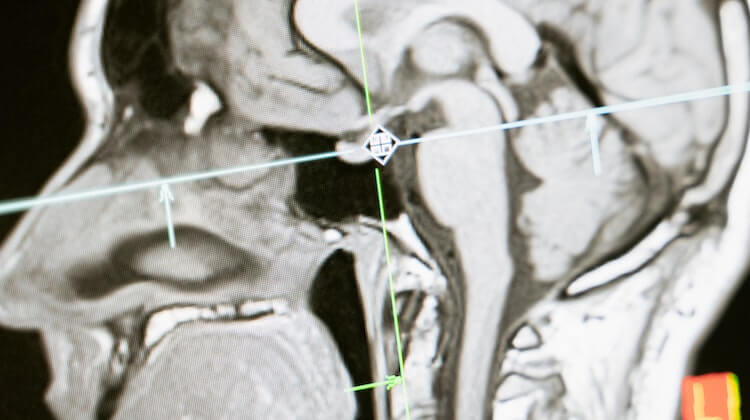

Brain-eating Amoeba Kya Hai: ब्रेन-खाने वाले अमीबा, जिसे हिंदी में “मस्तिष्क-खाने वाली अमीबा” भी कहा जाता है, एक सिंगल-सेलड जीवाणु है जो नेगलेरिया फावलेरी (Naegleria fowleri) नाम से पुकारा जाता है। यह जीवाणु प्राकृतिक जलमण्डलों में पाया जाता है, जैसे कि झीलें, नदियाँ और गर्म झरने। यह अमीबा नैगलेरिया फावलेरी संक्रमण का प्रमुख कारक होती है जो मानवों में मस्तिष्क संक्रमण का कारण बनती है।

ब्रेन-खाने वाले अमीबा क्या है: जब यह अमीबा प्राकृतिक जलमंडलों में मौजूद रहती है, तो यह अक्रिय रूप से रहती है। लेकिन जब यह मानव शरीर में प्रवेश करती है, तो यह तेजी से विकसित होकर मस्तिष्क के ऊपरी हिस्से तक पहुंचती है। यहाँ तक कि यह अमीबा आंतरिक कान के नसों के माध्यम से मस्तिष्क तक आ सकती है।

Brain-eating Amoeba Kya Hai: जब यह अमीबा मस्तिष्क में पहुंचती है, तो यहाँ वह न्यूरोन्स को खा जाती है और मस्तिष्क के ऊपरी हिस्से को नष्ट करती है। इसके परिणामस्वरूप गंभीर संक्रमण प्रकाशित होता है, जिसे नेगलेरिया मेनिंजाइटिस कहा जाता है।